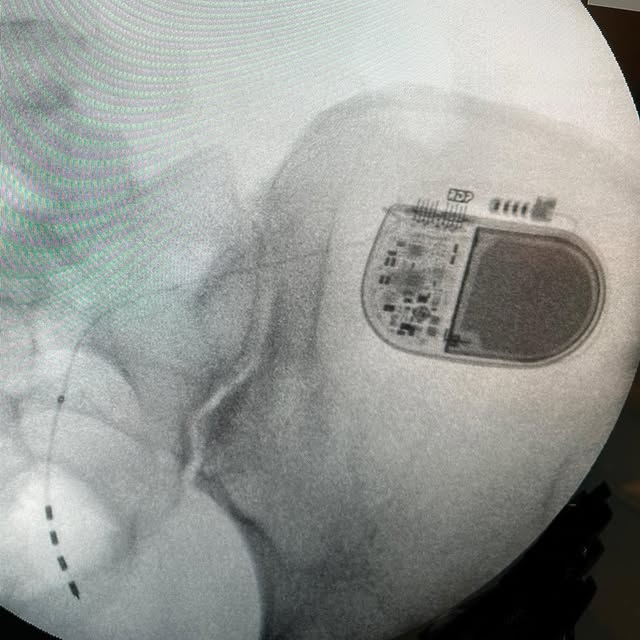

2024-09-13

**Years of chronic back and leg pain, minimal relief from therapies, and even surgery couldn’t help this patient. Finally, a breakthrough: after trying a spinal cord stimulation (SCS) trial using a closed-loop system, they experienced *over 70% pain relief* 🙌.** Closed-loop systems have long been used in pacemakers, but it wasn’t until recently that this advanced technology was applied to SCS. Saluda Medical was the pioneer in this field, publishing a groundbreaking study in *The Lancet Neurology* showing its superior results compared to traditional tonic SCS. To read more, check out the article here: https://www.thelancet.com/journals/laneur/article/PIIS1474-4422(19)30414-4/abstract 🔗 #ChronicPain #BackPainRelief #SpinalCordStimulation #SaludaMedical #PainManagement #Neuromodulation #InnovationInMedicine #BackSurgery #ClosedLoopSystem #nerveandpain #interventionalneurology #pain #painrelief